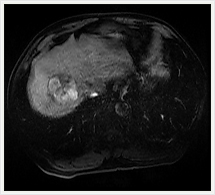

肝臓ダイナミック撮影

当院では、肝腫瘍を疑った場合MRI検査用のEOB・プリモビスト造影剤を使用して検査しています。造影剤を急速静注しながら連続撮影するダイナミック撮像では、造影剤注入30秒後に血流の豊富な部位(腫瘍など)を撮影する動脈相、3分後に造影剤は肝臓の正常な部位に分布し、最初に造影された血流の豊富な部位での造影剤の濃度が下がる平衡相を撮影しています。

EOB・プリモビストは正常な肝細胞に取り込まれ、転移性肝癌やほとんどの肝細胞癌など肝細胞機能を持たない組織には取り込まれない特徴があります。そのため、15分後に撮影すると、正常な機能を持った肝細胞だけが強く造影され、肝細胞機能を持たない異常な組織をより明確に見分けることができます。